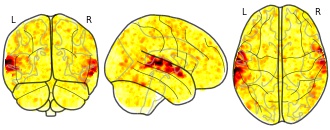

License information was derived automaticallyDescriptionCollection description

The individual Brain Charting (IBC) Project is using high resolution fMRI to map 13 subjects that undergo a large number of tasks: the HCP tasks, the so-called ARCHI tasks, a specific language task, video watching, low-level visual stimulation etc. The native resolution of the data is 1.5mm isotropic. Their main value lies in the large number of contrasts probed, the level of detail and the high SNR per subject. This dataset is meant to provide the basis of a functional brain atlas. We upload here smoothed individual SPMs. The uploaded maps comprise session-specific and fixed effects across maps acquired with AP and PA phase encoding directions.

Note that Neurovault collection #4438 is a subset of that one. In the present collections, some details have been fixed, including mroe accurate and unique file naming.

Subject species

homo sapiens

Modality

fMRI-BOLD

Analysis level

single-subject

Cognitive paradigm (task)

Pain-matrix narrative localizer

Map type

Z

License information was derived automaticallyDescriptionCollection description

The individual Brain Charting (IBC) Project is using high resolution fMRI to map 13 subjects that undergo a large number of tasks: the HCP tasks, the so-called ARCHI tasks, a specific language task, video watching, low-level visual stimulation etc. The native resolution of the data is 1.5mm isotropic. Their main value lies in the large number of contrasts probed, the level of detail and the high SNR per subject. This dataset is meant to provide the basis of a functional brain atlas. We upload here smoothed individual SPMs. The uploaded maps comprise session-specific and fixed effects across maps acquired with AP and PA phase encoding directions.

Note that Neurovault collection #4438 is a subset of that one. In the present collections, some details have been fixed, including mroe accurate and unique file naming.

Subject species

homo sapiens

Modality

fMRI-BOLD

Analysis level

single-subject

Cognitive paradigm (task)

Mental time travel task

Map type

Z